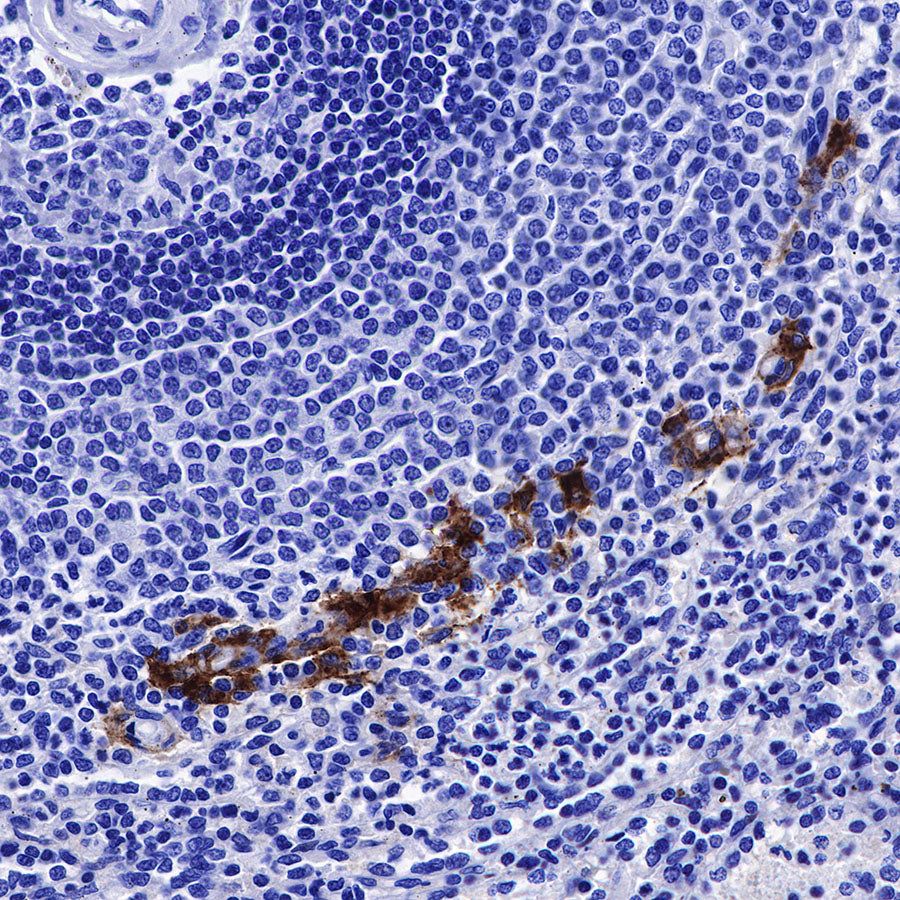

IHC shows positive staining in paraffin-embedded human Hodgkin's lymphoma. Anti-CD169 antibody was used at 1/250 dilution, followed by a HRP Polymer for Mouse & Rabbit IgG (ready to use). Counterstained with hematoxylin. Heat mediated antigen retrieval with Tris/EDTA buffer pH9.0 was performed before commencing with IHC staining protocol.